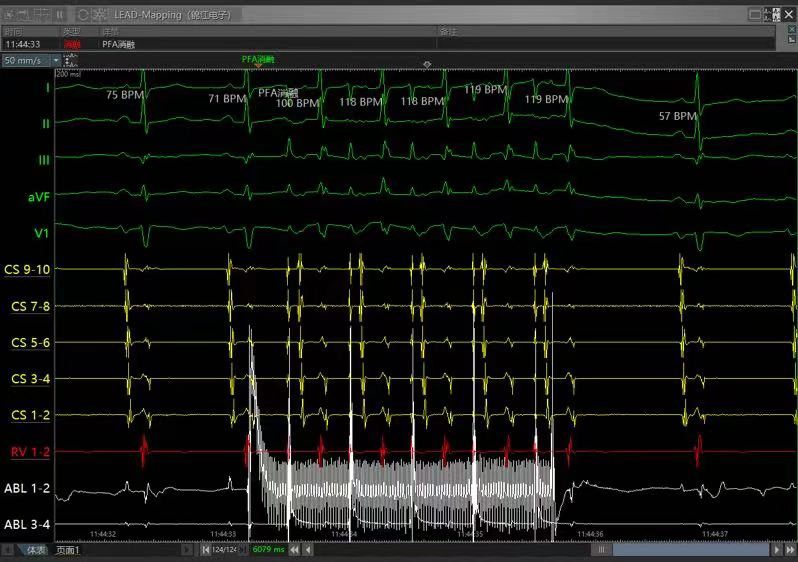

消融完成后无跳跃和回波

pfa多组消融图